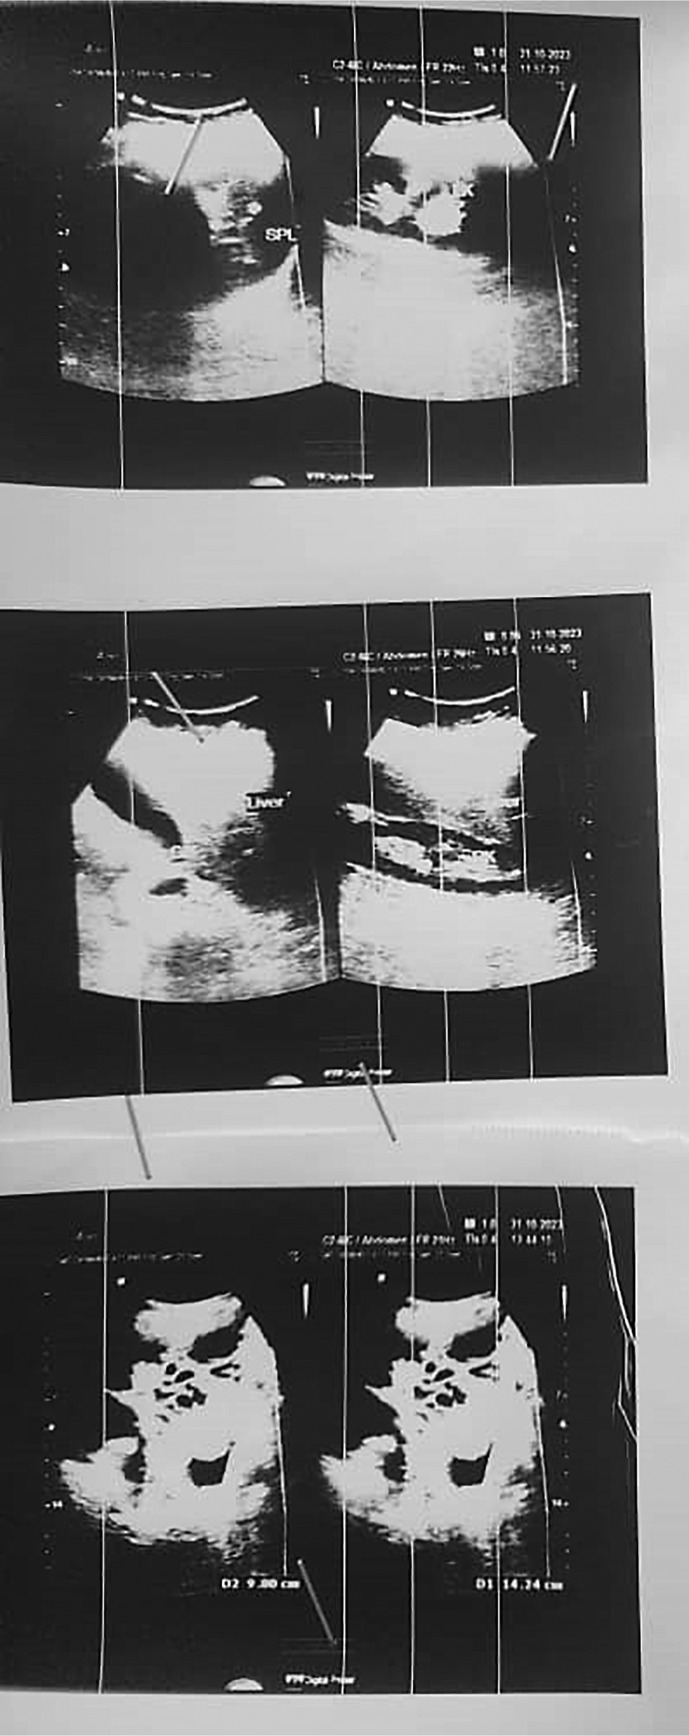

Case presentation: A 54-year-old Arab woman, a long-term smoker, presented with a 3-month history of abdominal pain, weight loss, and distension. Imaging revealed bilateral adnexal masses (left: 14 cm; right: 13 cm) with cystic degeneration, while tumor markers (CA-125, CEA) remained normal. Exploratory laparotomy identified bilateral ovarian tumors and omental metastasis. Histopathology confirmed a high-grade malignant BT, supported by immunohistochemistry. The patient underwent total hysterectomy, bilateral salpingo-oophorectomy, omentectomy, and six cycles of carboplatin-paclitaxel chemotherapy. Surveillance imaging at 8 months showed no recurrence.